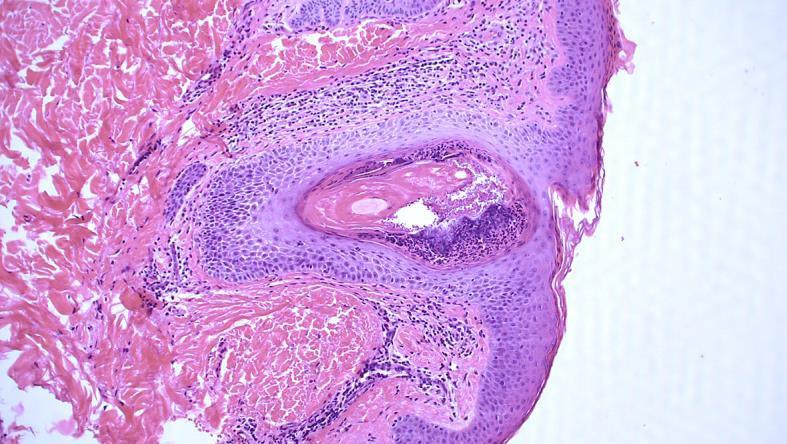

A report on a 40-year-old patient with recalcitrant, suppurative folliculitis is presented. After years of unsuccessful treatment with conventional therapies, the patient was diagnosed with adrenal insufficiency with a low level of circulating cortisol. A few weeks after the patient was subjected to substitution therapy with hydrocortisone, his folliculitis resolved. We discuss the role of plasma cortisol level in the pathogenesis of folliculitis.

本文报告了一名40岁患有顽固性化脓性毛囊炎的患者。在接受多年传统治疗但未成功后,该患者被诊断为肾上腺功能不全,循环皮质醇水平较低。在患者接受氢化可的松替代治疗几周后,其毛囊炎得到缓解。我们讨论了血浆皮质醇水平在毛囊炎发病机制中的作用。